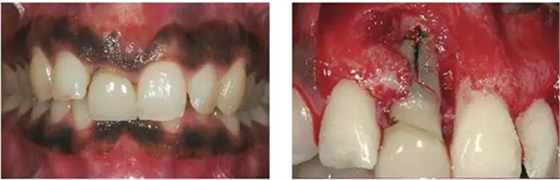

圖1、該病例顯示了厚齦生物型和中弧線形齦乳頭形態(tài)。右上中切牙由于牙根縱裂而需要拔除。由于該患牙伸長,使得軟組織量垂直向增加。牙齦色素沉著是個美學挑戰(zhàn)。

圖2、翻開全厚瓣可見明顯的牙根縱裂,唇側骨板2/3受到累及而缺損。